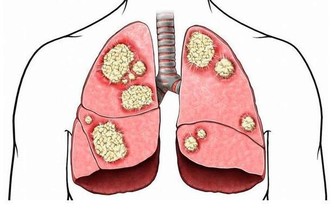

葫蘆素(英語:Cucurbitacin)是從中藥中提取,可治療肝炎及肝癌,存在於深綠色果類或果蒂部位,但誤食過量會有噁心、嘔吐、腹瀉等胃腸道症狀

人們在食用黃瓜時,因黃瓜把兒味苦而往往將其丟棄。其實,這種苦味是由其中含的一種叫葫蘆素的物質引起的,而葫蘆素C是難得的排毒養顏物質。更重要的是,葫蘆素可阻止肝細胞脂肪變性,抑制肝纖維增生,從而可預防原發性肝癌。

黃瓜中含有的葫蘆素C具有提高人體免疫功能的作用,達到抗腫瘤目的。此外,該物質還可治療慢性肝炎和遷延性肝炎,對原發性肝癌患者有延長生存期作用。